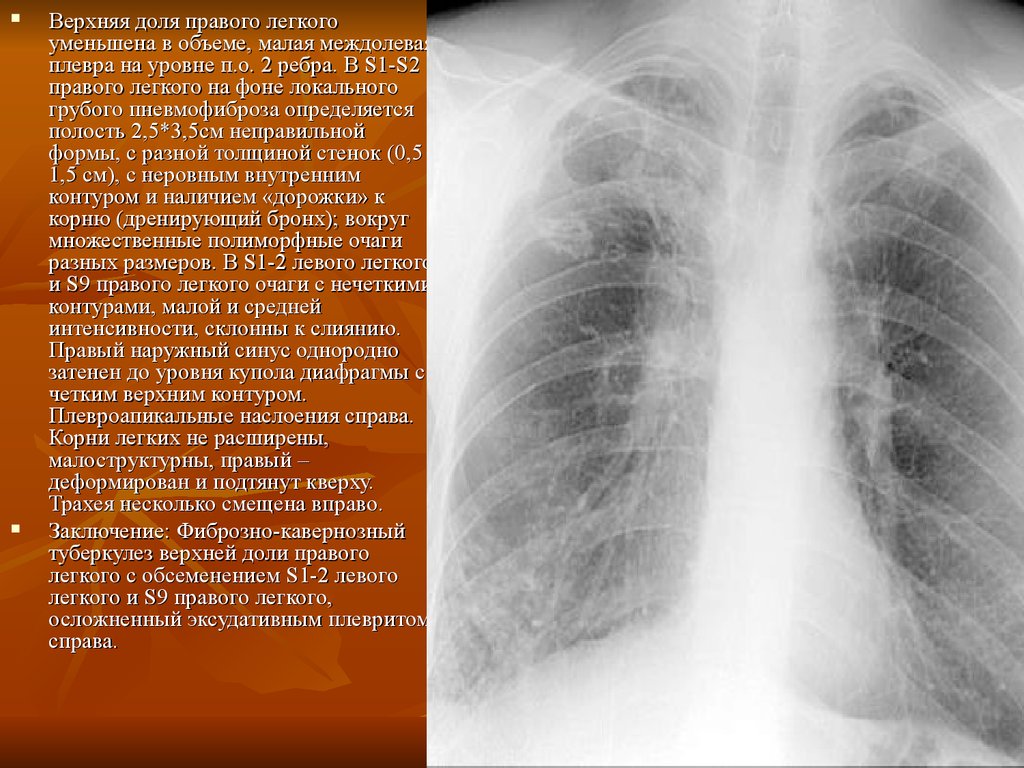

Рентгеновские снимки при врожденной эмфиземе легкого

Раздел: Визуальные уроки